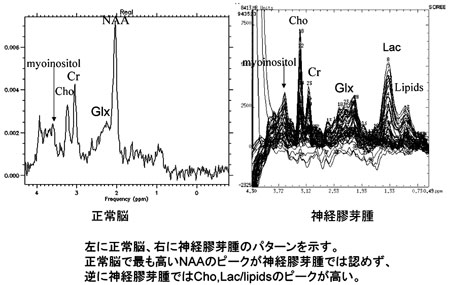

イラストレイテッド 脳腫瘍外科学 | 書籍詳細 | 書籍 | 医学書院, 沖縄県医師会_沖縄県医師会報(2012年4月号),

沖縄県医師会_沖縄県医師会報(2012年4月号), 日本脳腫瘍学会オフィシャルホームページ! Welcome to Japan,